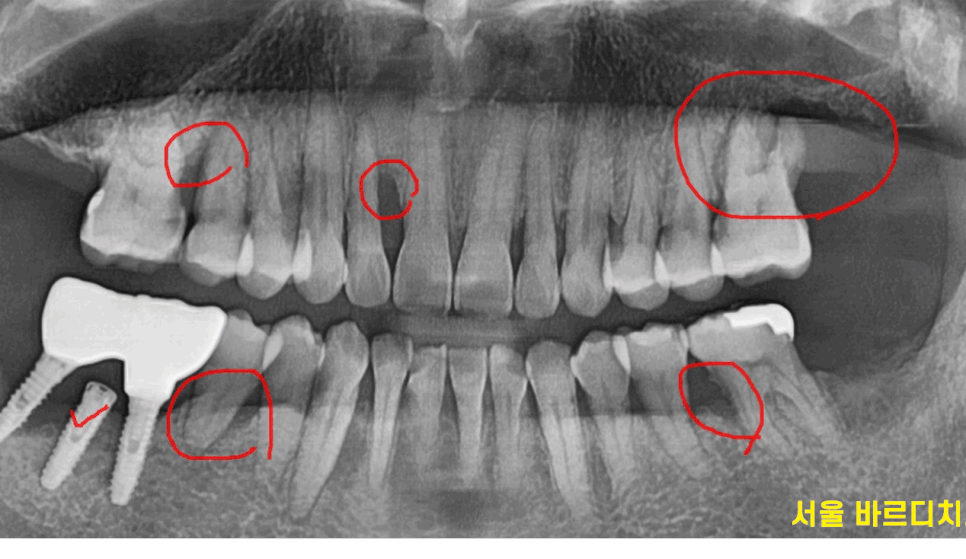

잇몸 뼈가 많이 녹은 x - ray를 보여드릴께요~

240430

빨간색 동그라미 친 부분이

잇몸뼈가 다 녹은 부분입니다.

이 정도가 되면 사실은 이를 뽑아야하는데요.